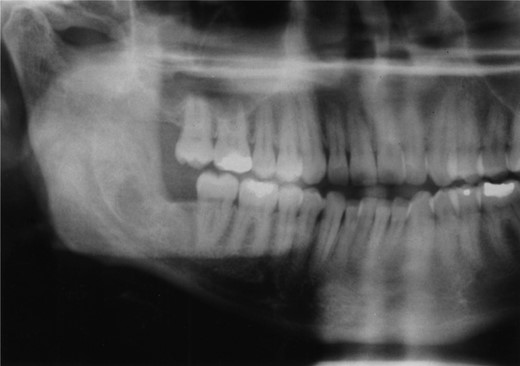

A decision was made to decompress the lesion to try and shrink the cystic space, encouraging bony infill. Over the following 3 months the patient underwent a further three re-packing procedures with irrigation of the cavity. The site of the cyst and difficulty of access necessitated general anaesthesia. The patient was admitted on one occasion for intra-venous antibiotics following an acute infective episode affecting the area. During the third operative procedure a split nasopharyngeal tube was inserted into the cyst cavity and sutured in position (Fig. 2). The patient was encouraged to flush the cavity clean through the tube drain.

Radiographic examination over the following few months showed new bone formation and within 9 months of the initial biopsy the drain was expelled by formation of new bone (Fig. 3). One year after the commencement of treatment the patient was admitted for enucleation of the cystic remnant. At the time of this procedure a small cyst was removed from the right upper ramus and condylar neck, together, with a separate cyst associated with the lower right wisdom tooth. The patient made an uneventful post-operative recovery and histology revealed two KCOTs with a thick parakeratinized type of epithelium typical of radicular cysts.

Demonstrates bony infill with the nasopharyngeal tube in place.